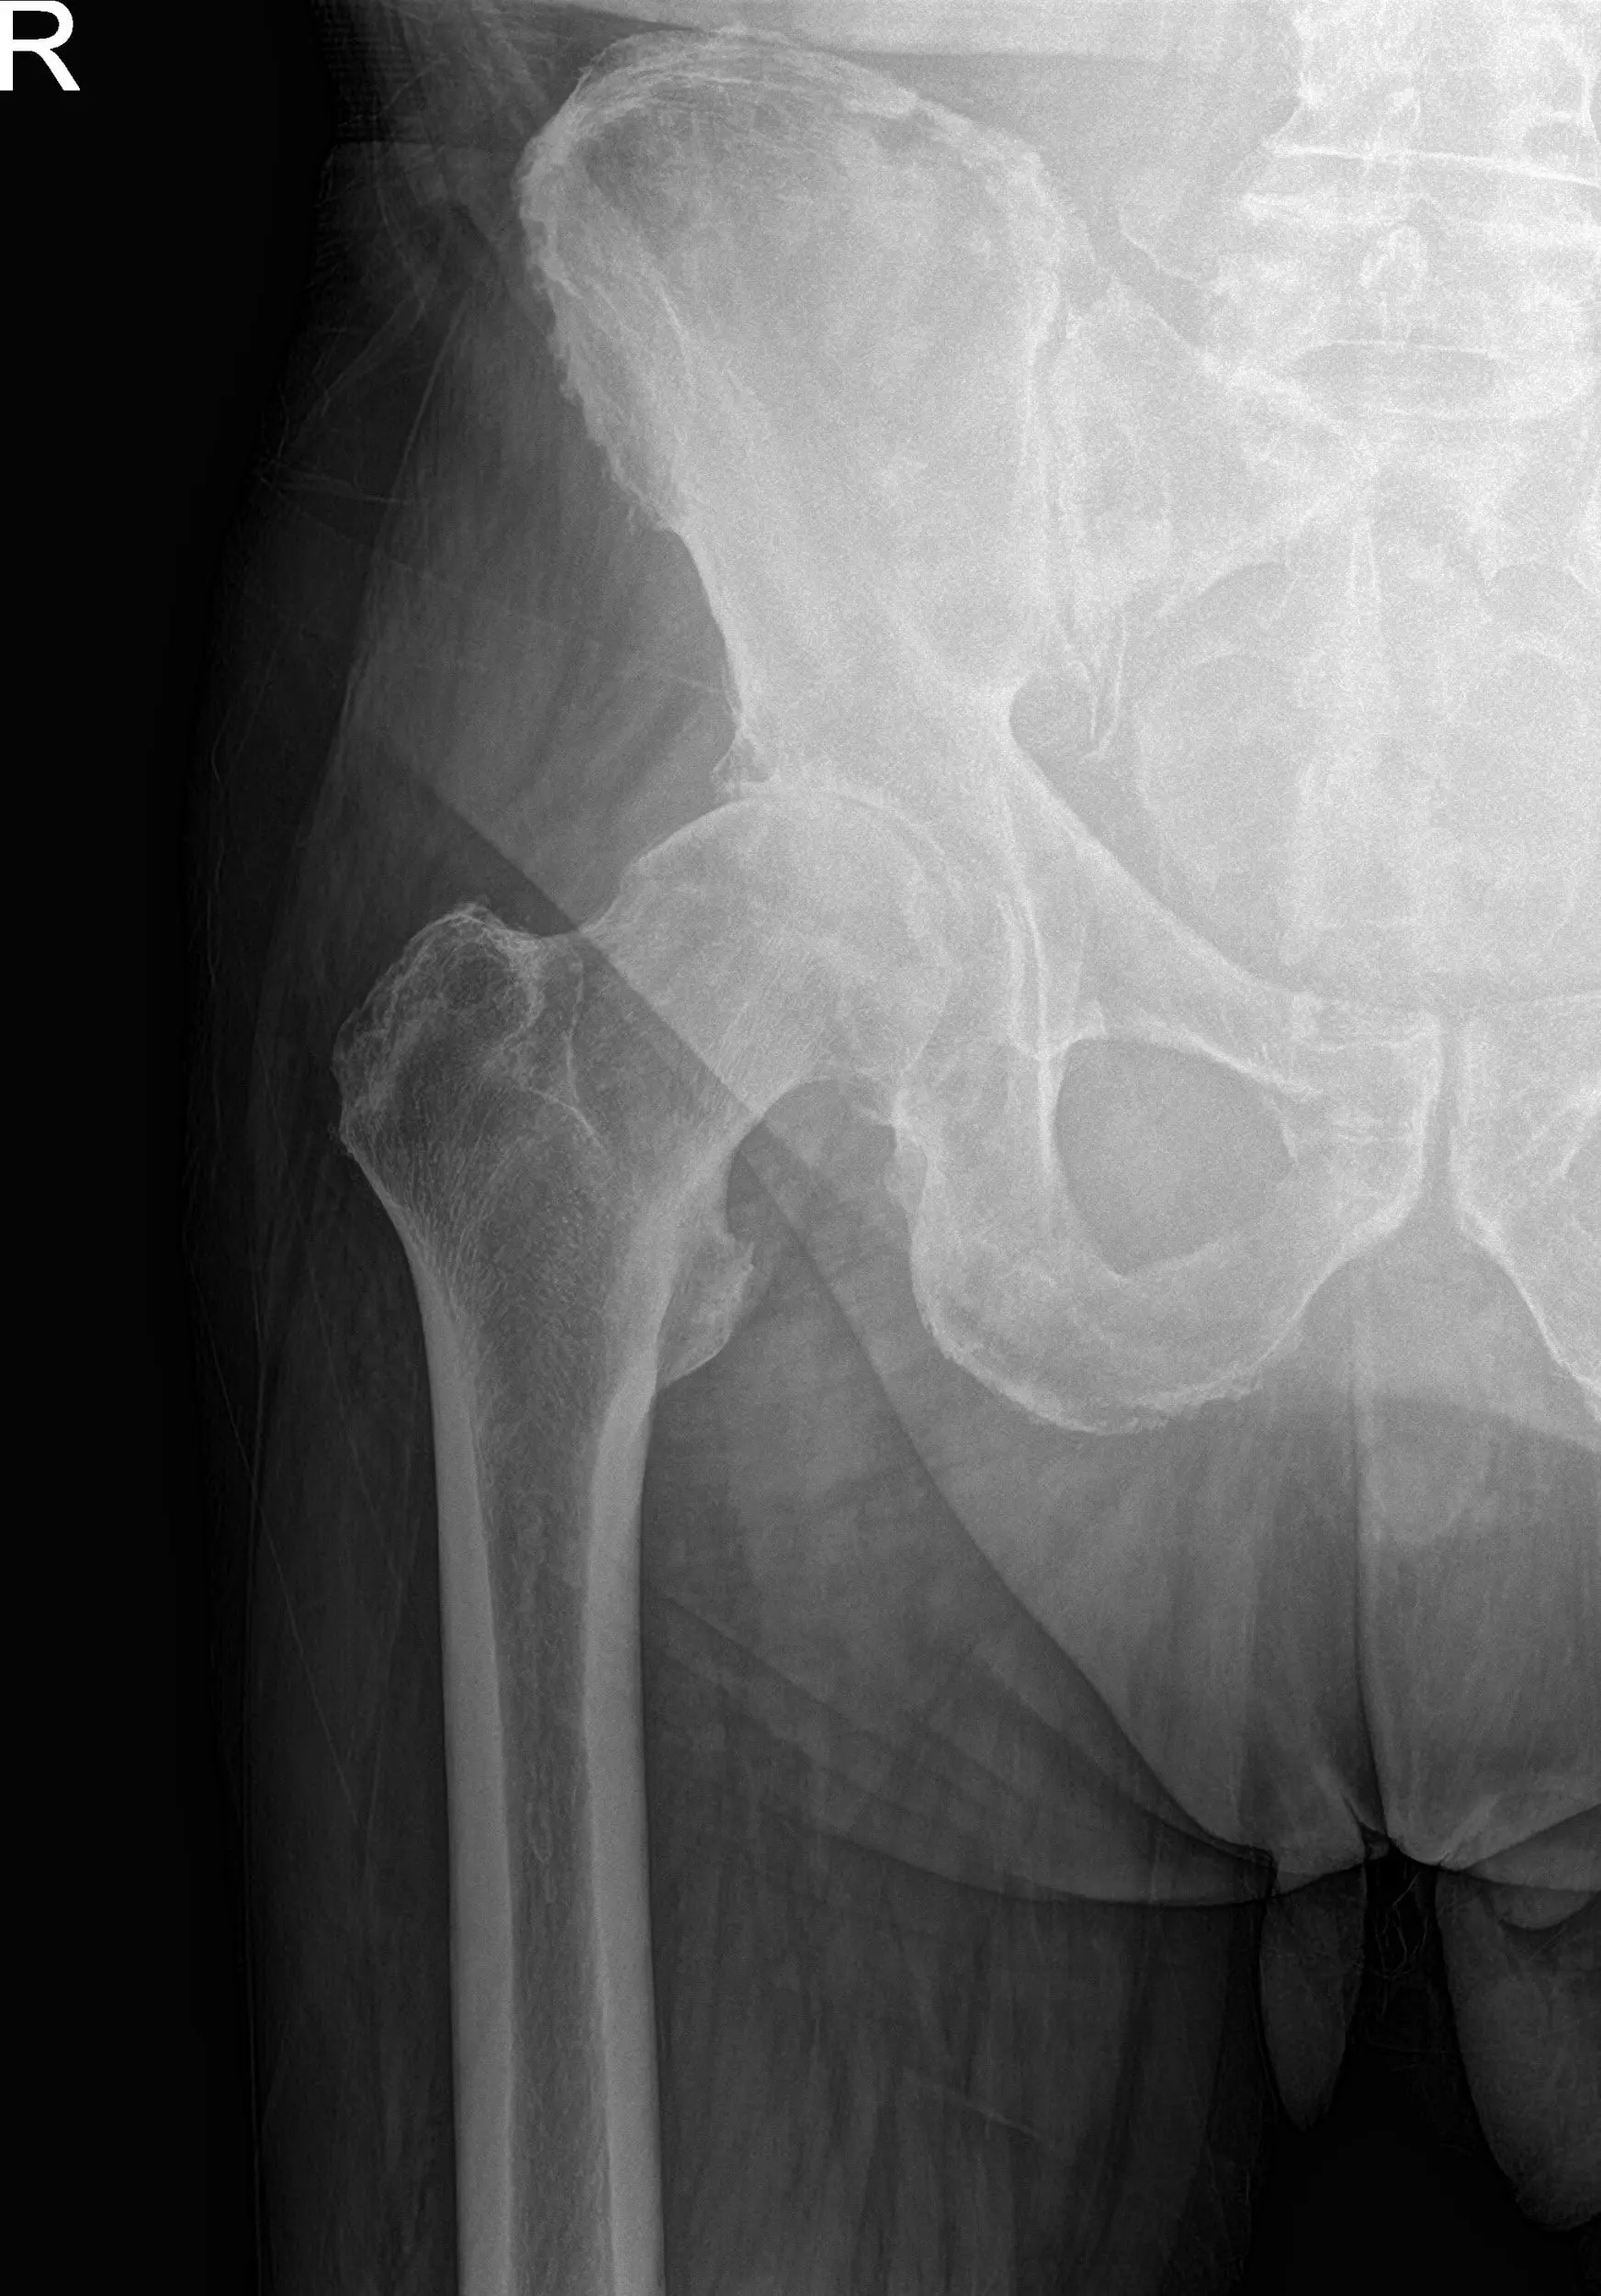

Preoperative X-ray images showing AP and frog-leg lateral view of the right hip